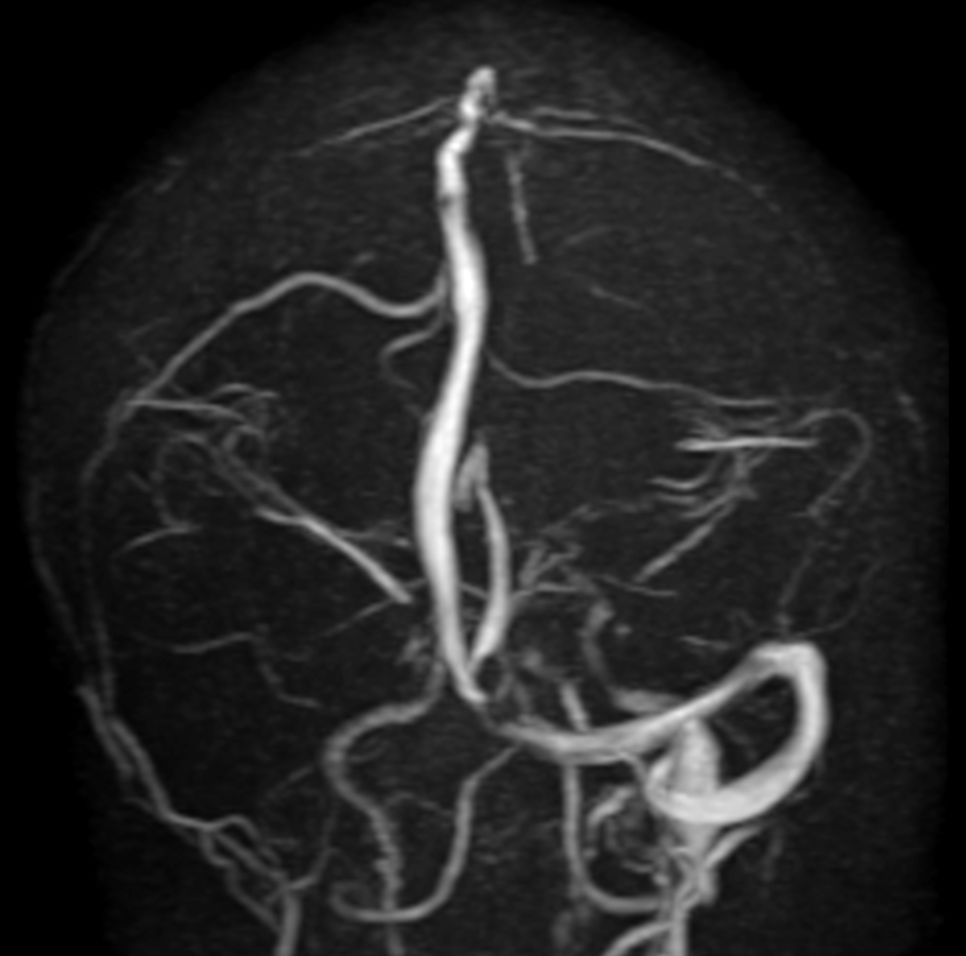

Pediatric Brain with hemorrhagic mass

Pediatric patient with a hemorrhagic mass in the brain